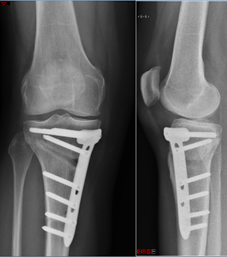

Hohe Tibiaosteotomie (Unterschenkel) links.

Beispiel einer hohen Tibiaosteotomie mit Tomofix-Plattensystem. Die oberen Bilder entsprechen der MRI-Bildgebung, im oberen linken Bild ist durch den roten Pfeil ein Knochenödem am Oberschenkel markiert. In der Ganzbeinaufnahme ist zu sehen, wie aus dem O-Bein ein X-Bein wurde. Die mechanische Beinachse (rot) wurde vom Innengelenk in das Aussengelenk des Knies verlagert